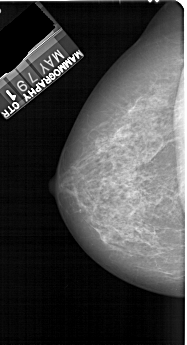

A_1894_1.RIGHT_MLO

RIGHT_MLO LINES 5296 PIXELS_PER_LINE 2926 BITS_PER_PIXEL 12 RESOLUTION 43.5 OVERLAY